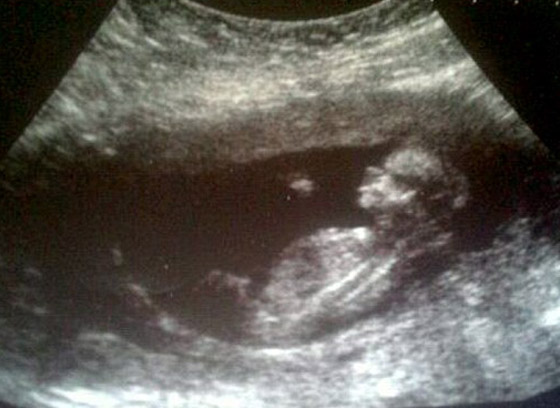

كانت سيري جريفثز قد أحبطت تماما عندما قال لها الاطباء انها اجهضت طفلتها. وقد خضعت لسلسلة فحوصات أكد لها الاطباء بعدها بأن طفلتها توفيت. لكن بالرغم من كل شيء فان سيري كانت مقتنعة تماما بأن ابنتها ما زالت حية بداخلها، وطلبت بأن يجروا لها فحص الموجات فوق الصوتية من أجل ان تتأكد. وكانت هذه الوالدة على حق بالفعل فقد تفاجأت الممرضات ان الطفلة حيّة وبصحة جيدة!

وقد احتفلت الطفلة مؤخرا بعيدها الاول في بيتها في استراليا مع والدتها ووالدها ستيف. وقالت الوالدة ان الرابط بين الام وجنينها قوي ولا يمكن للام أن تخطئ في مشاعرها بمثل هذه الأمور، حيث قالت: "كان الامر مرعبا حقا عندما قالوا لي ان طفلتي ميتة بداخلي، لكن شيء ما في داخلي قال لي ان ابنتي ليست ميتة بل ما زالت حية! فبقيت اٍسأل وأطلب من الاطباء بأن يجروا لي صورة وفحوصات من أجل التأكد، لكنهم كانوا يجيبونني بأن ابنتي توفيت ولا أمل".

وأضافت: "بعد ان أكدوا لي موت طفلتي قمت بالتوقيع على وثيقة من أجل حرق جثتها وكنت أبكي وارتجف، حتى استجابوا لطلبي وأجروا لي الفحص المطلوب، وتبين ان طفلتي حية ترزق بداخلي، شعرت بالسعادة والفرح من أجل ذلك وفي نفس الوقت شعرت بالغضب من خطأ الاطباء، وقاموا بعدها بالاعتذار لي، "أشكر الله كثيرا بانني لم أقم باجهاض طفلتي وقتلها".